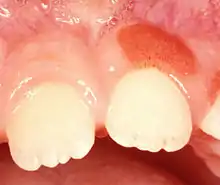

| Plasma cell gingivitis in an adult (histologically verified). | |

Plasma cell gingivitis appears as mild gingival enlargement and may extend from the free marginal gingiva on to the attached gingiva.[6] Sometimes it is blended with a marginal, plaque induced gingivitis, or it does not involve the free marginal gingiva. It may also be found as a solitude red area within the attached gingiva (pictures). In some cases the healing of a plaque-induced gingivitis or a periodontitis resolves a plasma cell gingivitis situated a few mm from the earlier plaque-infected marginal gingiva. In case of one or few solitary areas of plasma cell gingivitis, no symptoms are reported from the patient. Most often solitary entities are therefore found by the dentist.[2]